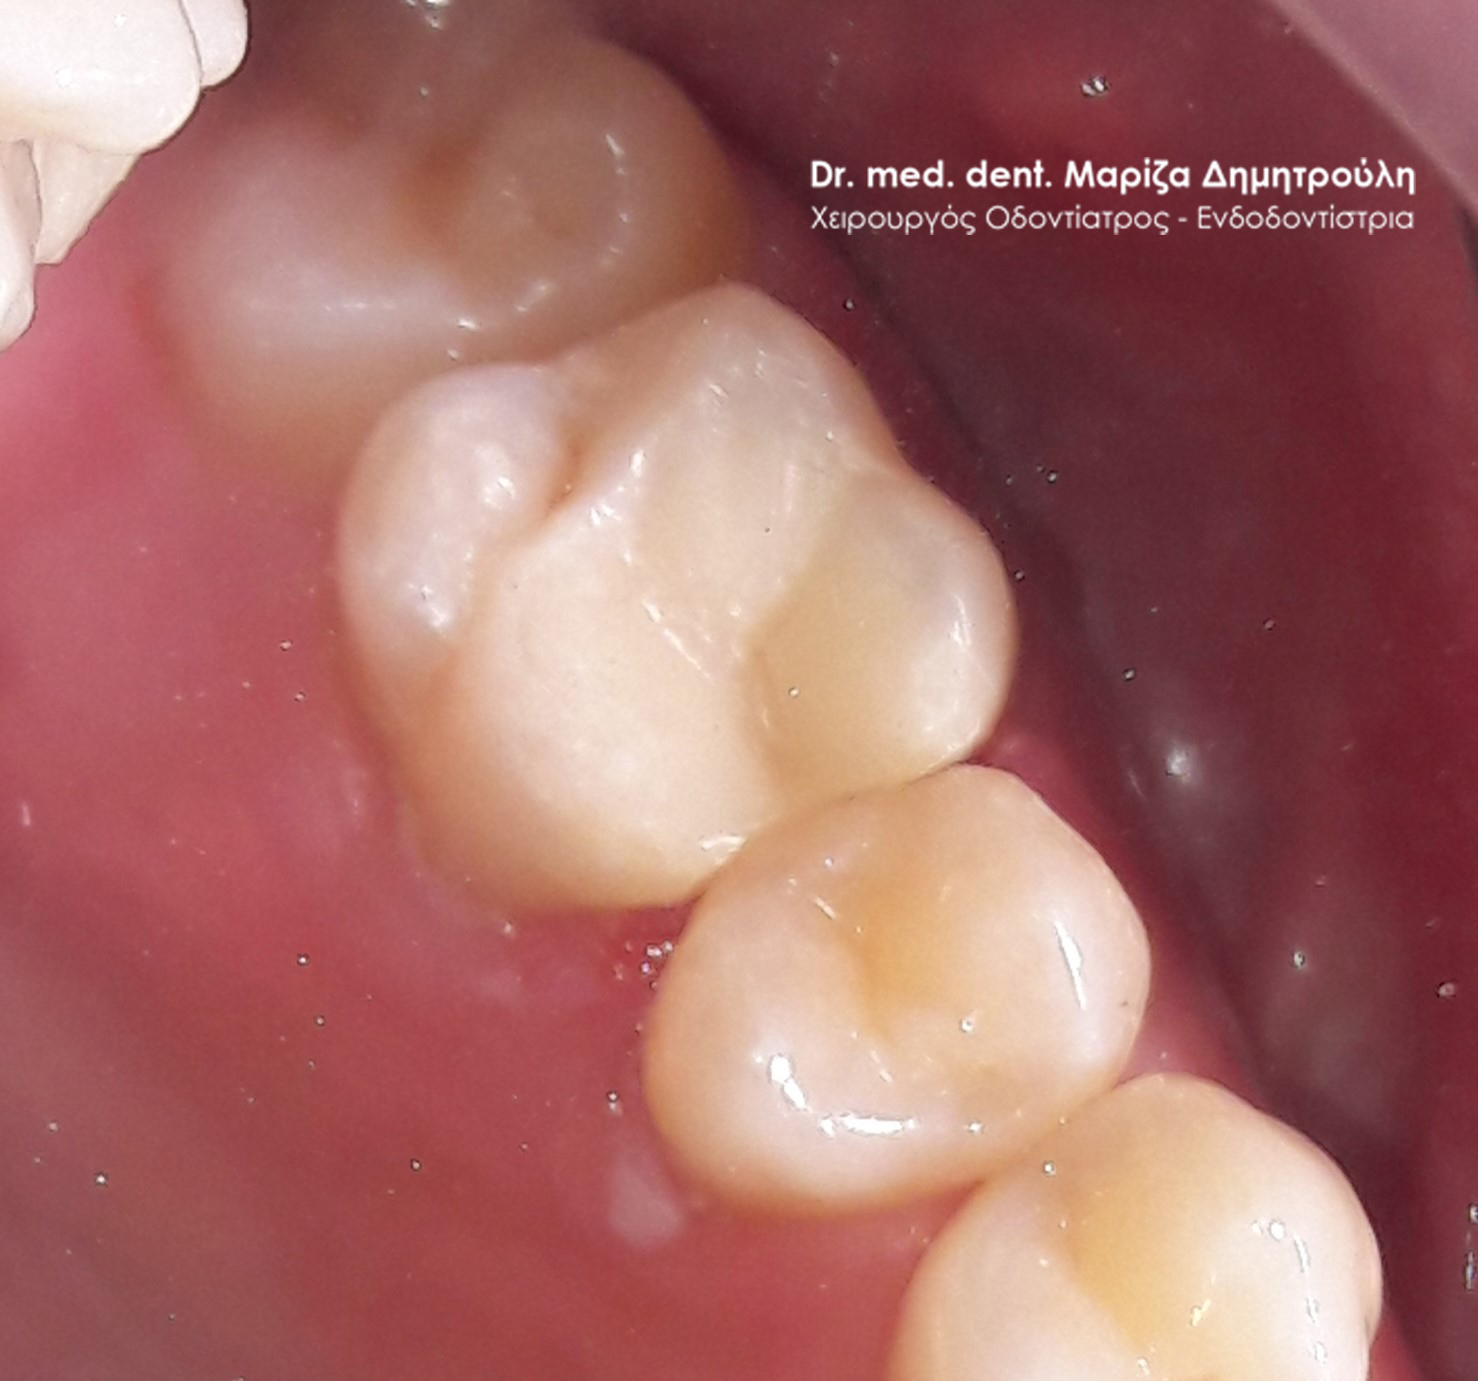

Περιστατικό – Λευκά σφραγίσματα δύο δοντιών

Στο παρόν περιστατικό απουσιάζει η αρχική εικόνα των δύο δοντιών πριν αρχίσει ο εκτροχισμός τους. Διαθέσιμες είναι μόνο η ενδιάμεση εικόνα που παρουσιάζει το εύρος του οδοντικού ελλείμματος στα δύο γομφίους της αριστερής πλευράς της άνω γνάθου και η τελική εικόνα αποκατάστασης των δύο δοντιών.

Η ασθενής αισθανόταν τις τελευταίες μέρες έναν ήπιο πόνο κατά τη μάσηση τροφών. Μετά την κλινική εξέταση του στόματος διαπιστώθηκε η ύπαρξη τερηδονικών κοιλοτήτων στους δύο άνω αριστερούς γομφίους. Αποφασίστηκε με τη συναίνεση της ασθενούς η αντικατάσταση των σφραγισμάτων. Στον πρώτο γομφίο διορθώθηκε μόνο η μισή έκταση του παλιού σφραγίσματος, καθώς κρίθηκε οτι δεν ήταν απαραίτητη η αφαίρεση ολόκληρου του παλιού σφραγίσματος.

ΠΡΙΝ

META